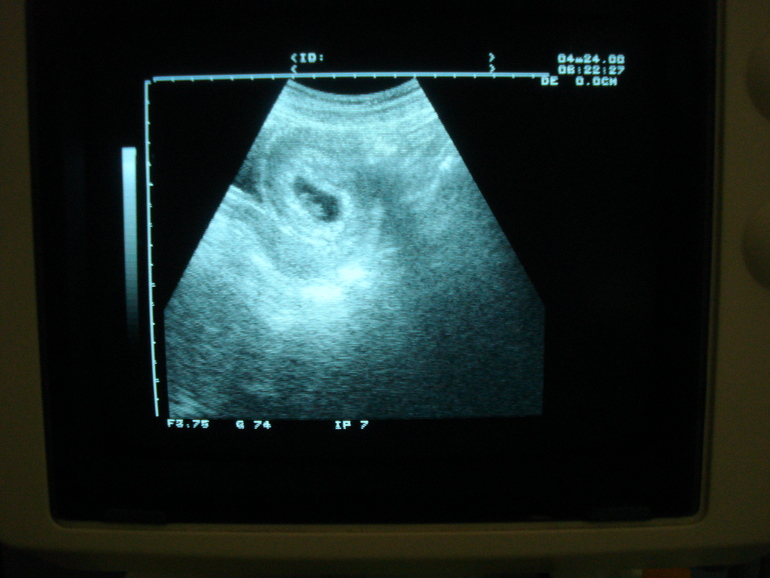

первое УЗИ

Вопросы про УЗИ, обследования и анализы: что, где, как, когда?Девочки, было ли у вас так, что вы пришли на первое узи примерно на 5 неделе, у вас нашли лодное яйцо, посмотрели прикрепление, а вот "начинку" этого яйца вроде как увидели, но не четко и как то все смазано что ли... А то сегодня ходила на первое УЗИ, и вот теперь сижу думаю.. То что в яйце что то есть- это точно, сама видела. Сказали придти недели через 2, говорят рановато пришла. Ждать понятное дело сил нет, но буду стараться. Все симптомы Б на лицо, выделений никаких нет, так что в этом плане вроде как все нормально. Было у кого нибудь так?